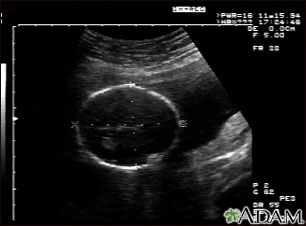

Ultrasonido de un feto normal; medidas de la cabeza

Ultrasonido normal a las 19 semanas de gestación. Por lo general los médicos prefieren disponer de las medidas fetales para verificar el tamaño del feto y para buscar anomalías. Este ultrasonido muestra las medidas de la cabeza fetal, señaladas por las líneas punteadas y las cruces.